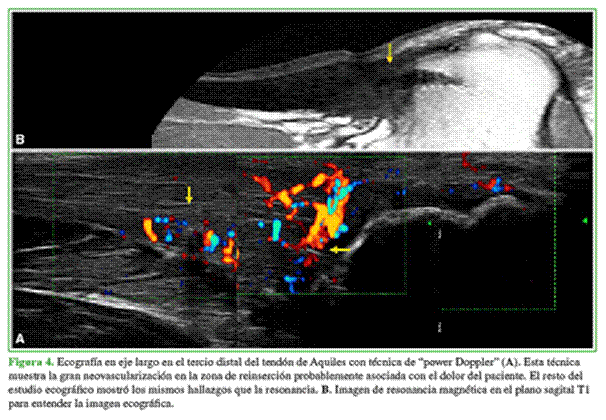

El paciente concurrió con varias RM que mostraban hallazgos similares sin poner de manifiesto el diagnóstico de su dolencia. Se decide completar el estudio con una ecografía con técnica de “power Doppler”. El estudio ecográfico convencional mostró los hallazgos conocidos en la RM; sin embargo, al agregar el “power Doppler”, se observa un aumento franco de la vascularización en la zona de reinserción (Figura 4).